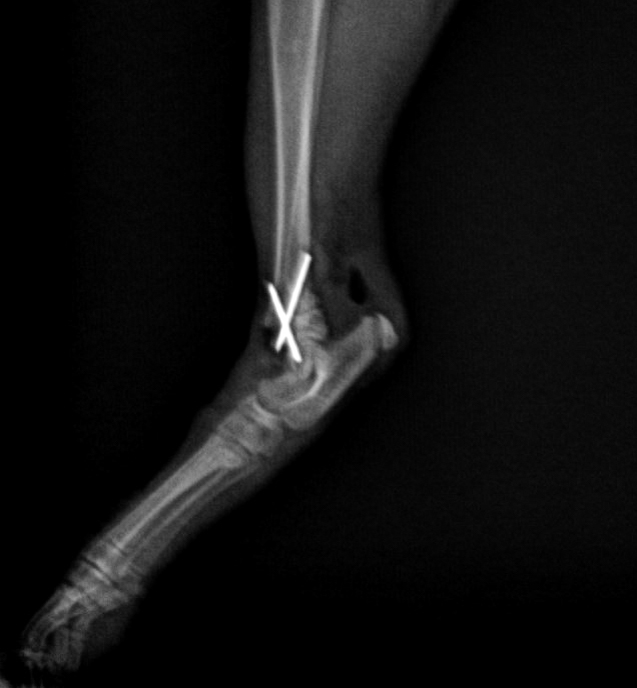

辛巴是一隻流浪小貓。在2016年12月被發現在垃圾收集站被狗咬傷,令他的右後腿嚴重骨折,傷口亦很深。善良的社工黃先生找到了他,並聯絡了Jack’s Veterinary。我們的獸醫Dr. Vincent Tse為了救回他,第一時間安排辛巴做手術。鰂魚涌獸醫診所的Dr. Jason Yew得知這個個案後,也很樂意借出手術房和設備。

手術前後的X光片對比,手術前可見明顯骨折,手術用鋼釘固定骨折位置

辛巴穩定後,兩位醫生很快就替他進行手術。手術非常順利。他在康復期間恢復得非常快。現在他長大了一點,走路跑步沒有任何問題,非常活躍。最高興的是,他後來獲一位非常愛錫他的主人收養,命名為辛巴。